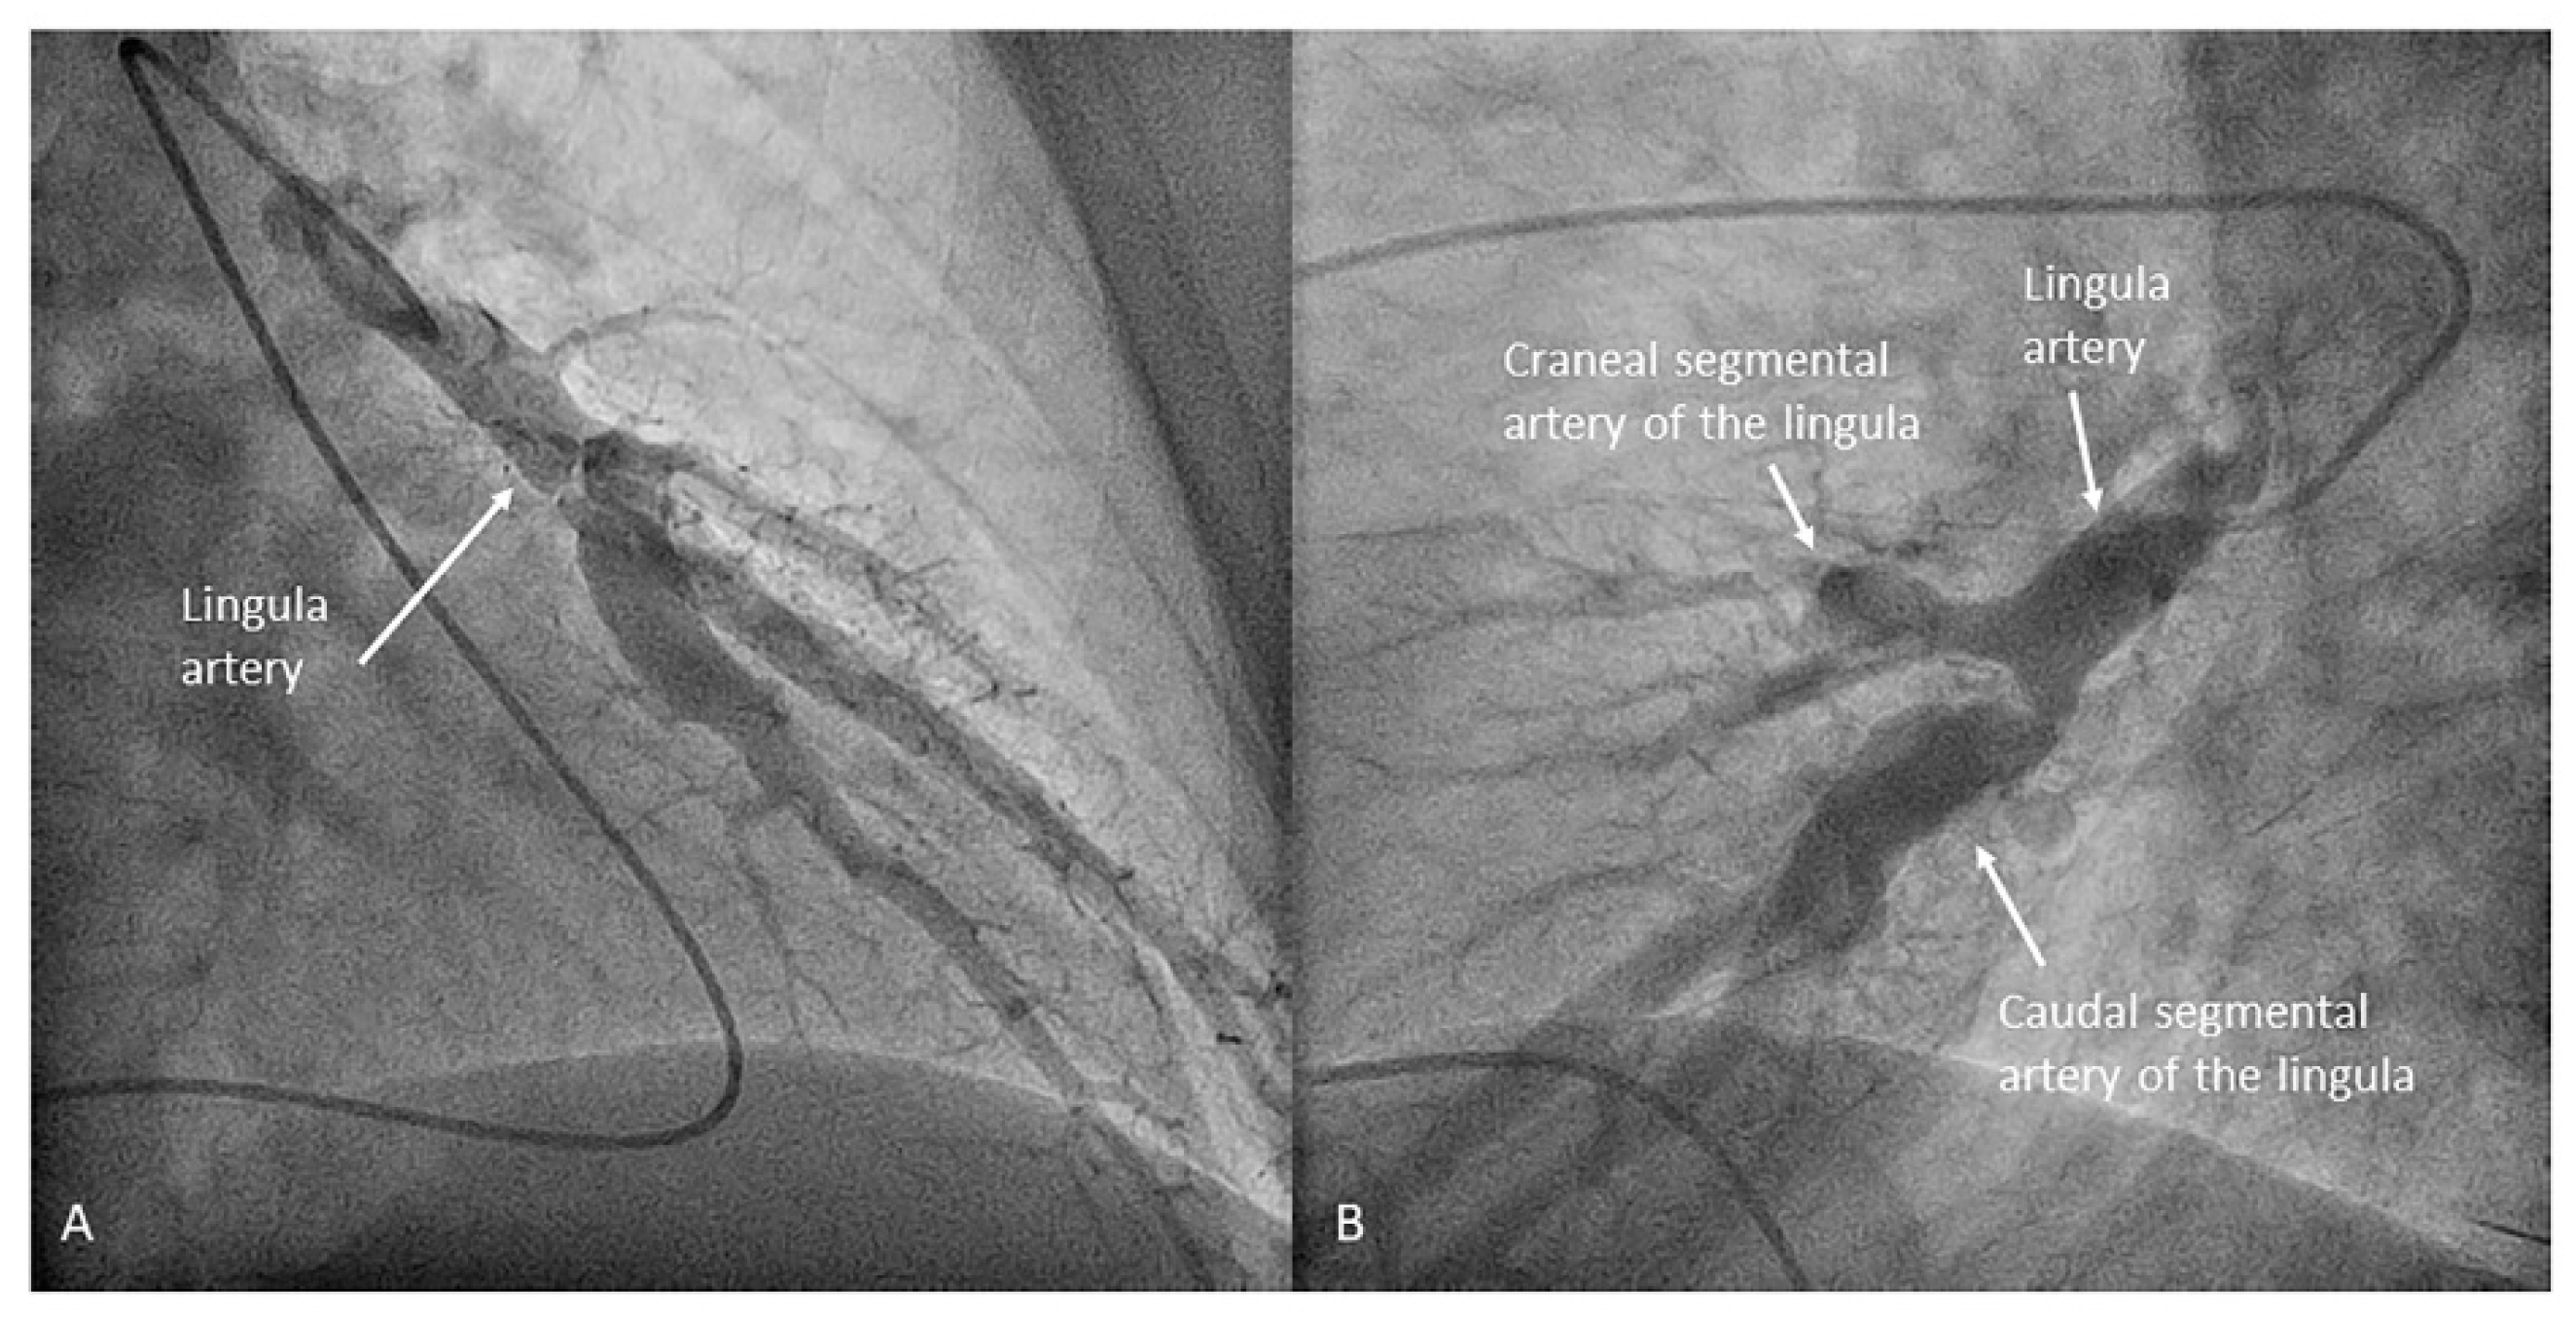

- Lingula. The lingula artery is easily cannulated in the AP view with the JL 3.5/4 catheter (depending on the PA dilatation). The maneuver and position in the AP view is the same as described for the anterior segmental artery of the left upper lobe (A3), though somewhat lower (Figure 25). Amplatz left 1 or 2 is also a good choice for catheterization of the lingula branches. In addition, this catheter gives extra support when performing BPA of these branches. The two lingula segmental arteries are well displayed in the lateral and in the cranial RAO/cranial AP views.